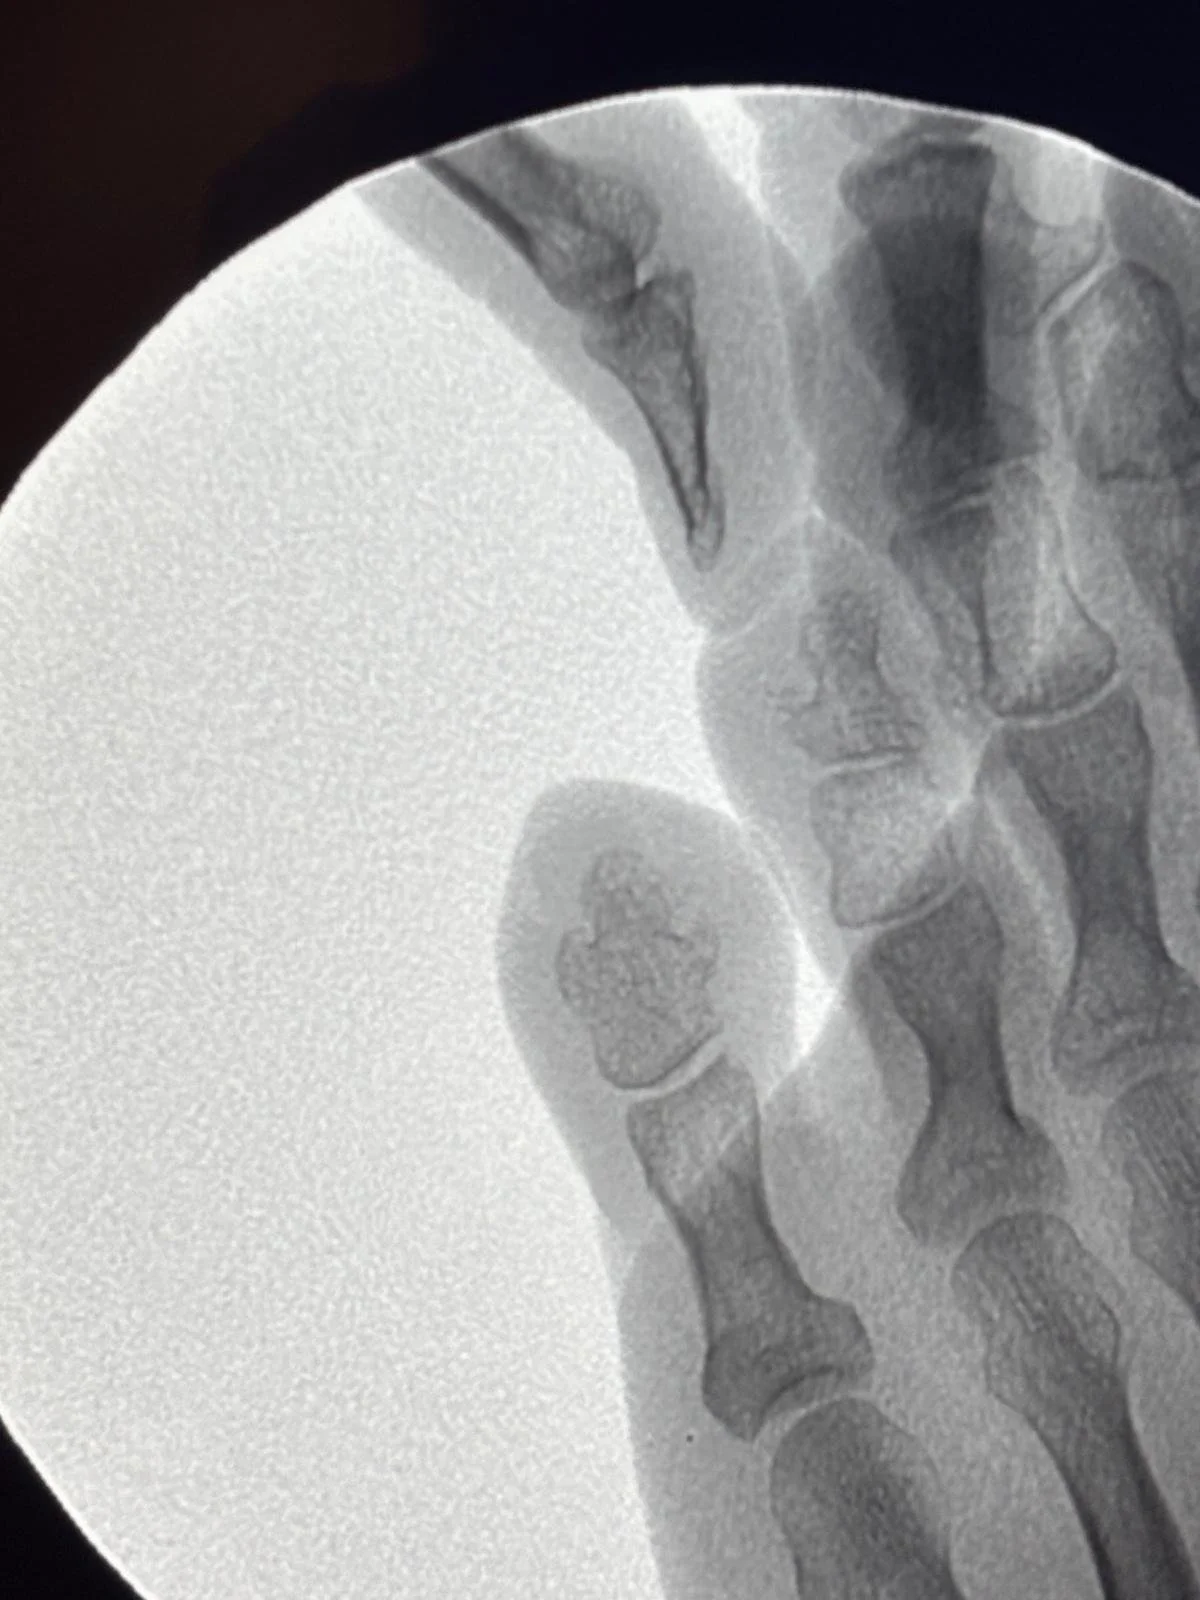

1. El diagnóstico por imagen (Pre-operatorio)

En la radiografía inicial (que puedes ver en el vídeo de nuestro Instagram), identificamos una exostosis o "pico de hueso" en la falange. Este crecimiento óseo anómalo es el verdadero culpable: genera una presión constante desde el interior contra el dedo adyacente, obligando a la piel a defenderse creando durezas.